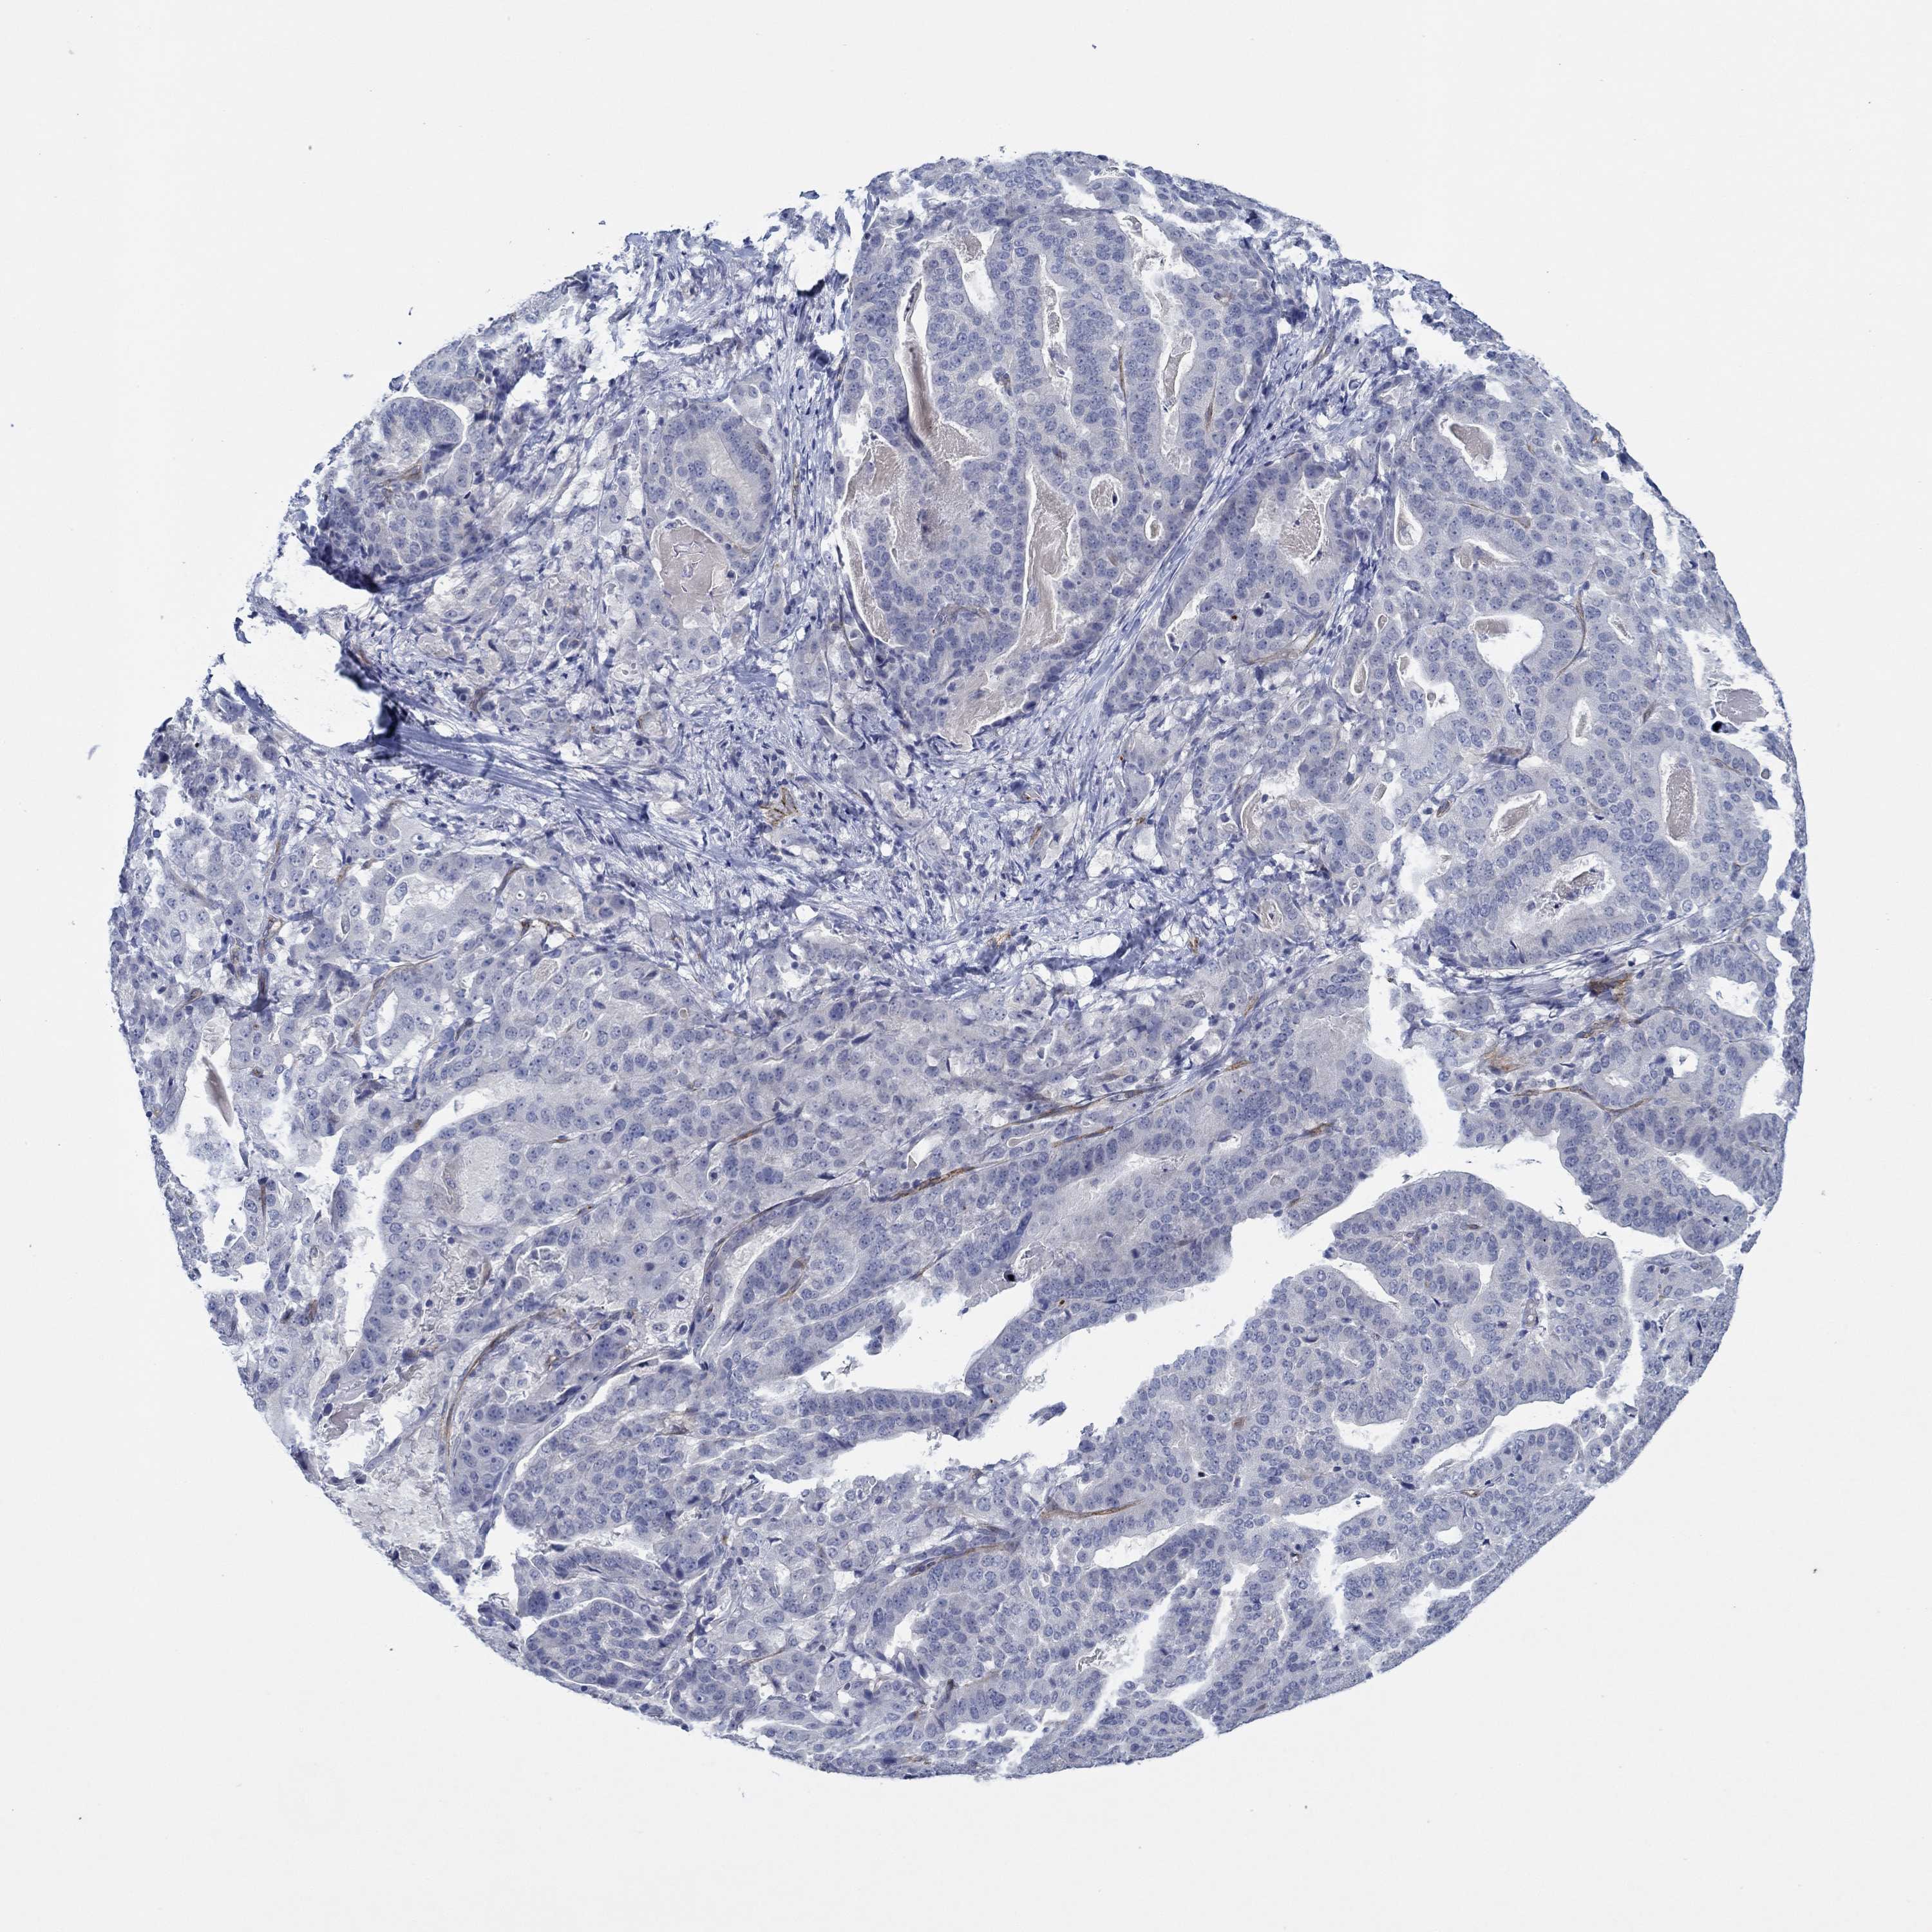

STOMACH CANCER - Protein expressioni

A mouse-over function shows sample information and annotation data. Click on an image to view it in a full screen mode. Samples can be filtered based on level of antibody staining by selecting one or several of the following categories: high, medium, low and not detected. The assay and annotation is described here.

Antibody stainingi

Antibody staining in the annotated cell types in the current human tissue is reported as not detected, low, medium, or high, based on conventional immunohistochemistry profiling in selected tissues. This score is based on the combination of the staining intensity and fraction of stained cells.

Each image is clickable and will lead to virtual microscopy that enables deeper exploration of all samples and also displays staining intensity scores, fraction scores and subcellular localization as well as patient and tissue information for each sample.

Antibody HPA071370

Antibody CAB013080

Staining

High

Medium

Low

Not detected

Intensity

Strong

Moderate

Weak

Negative

Quantity

>75%

75%-25%

<25%

None

Location

Nuclear

Cytoplasmic/membranous

Cytoplasmic/membranous,nuclear

Adenocarcinoma, NOS

Adenocarcinoma, High grade